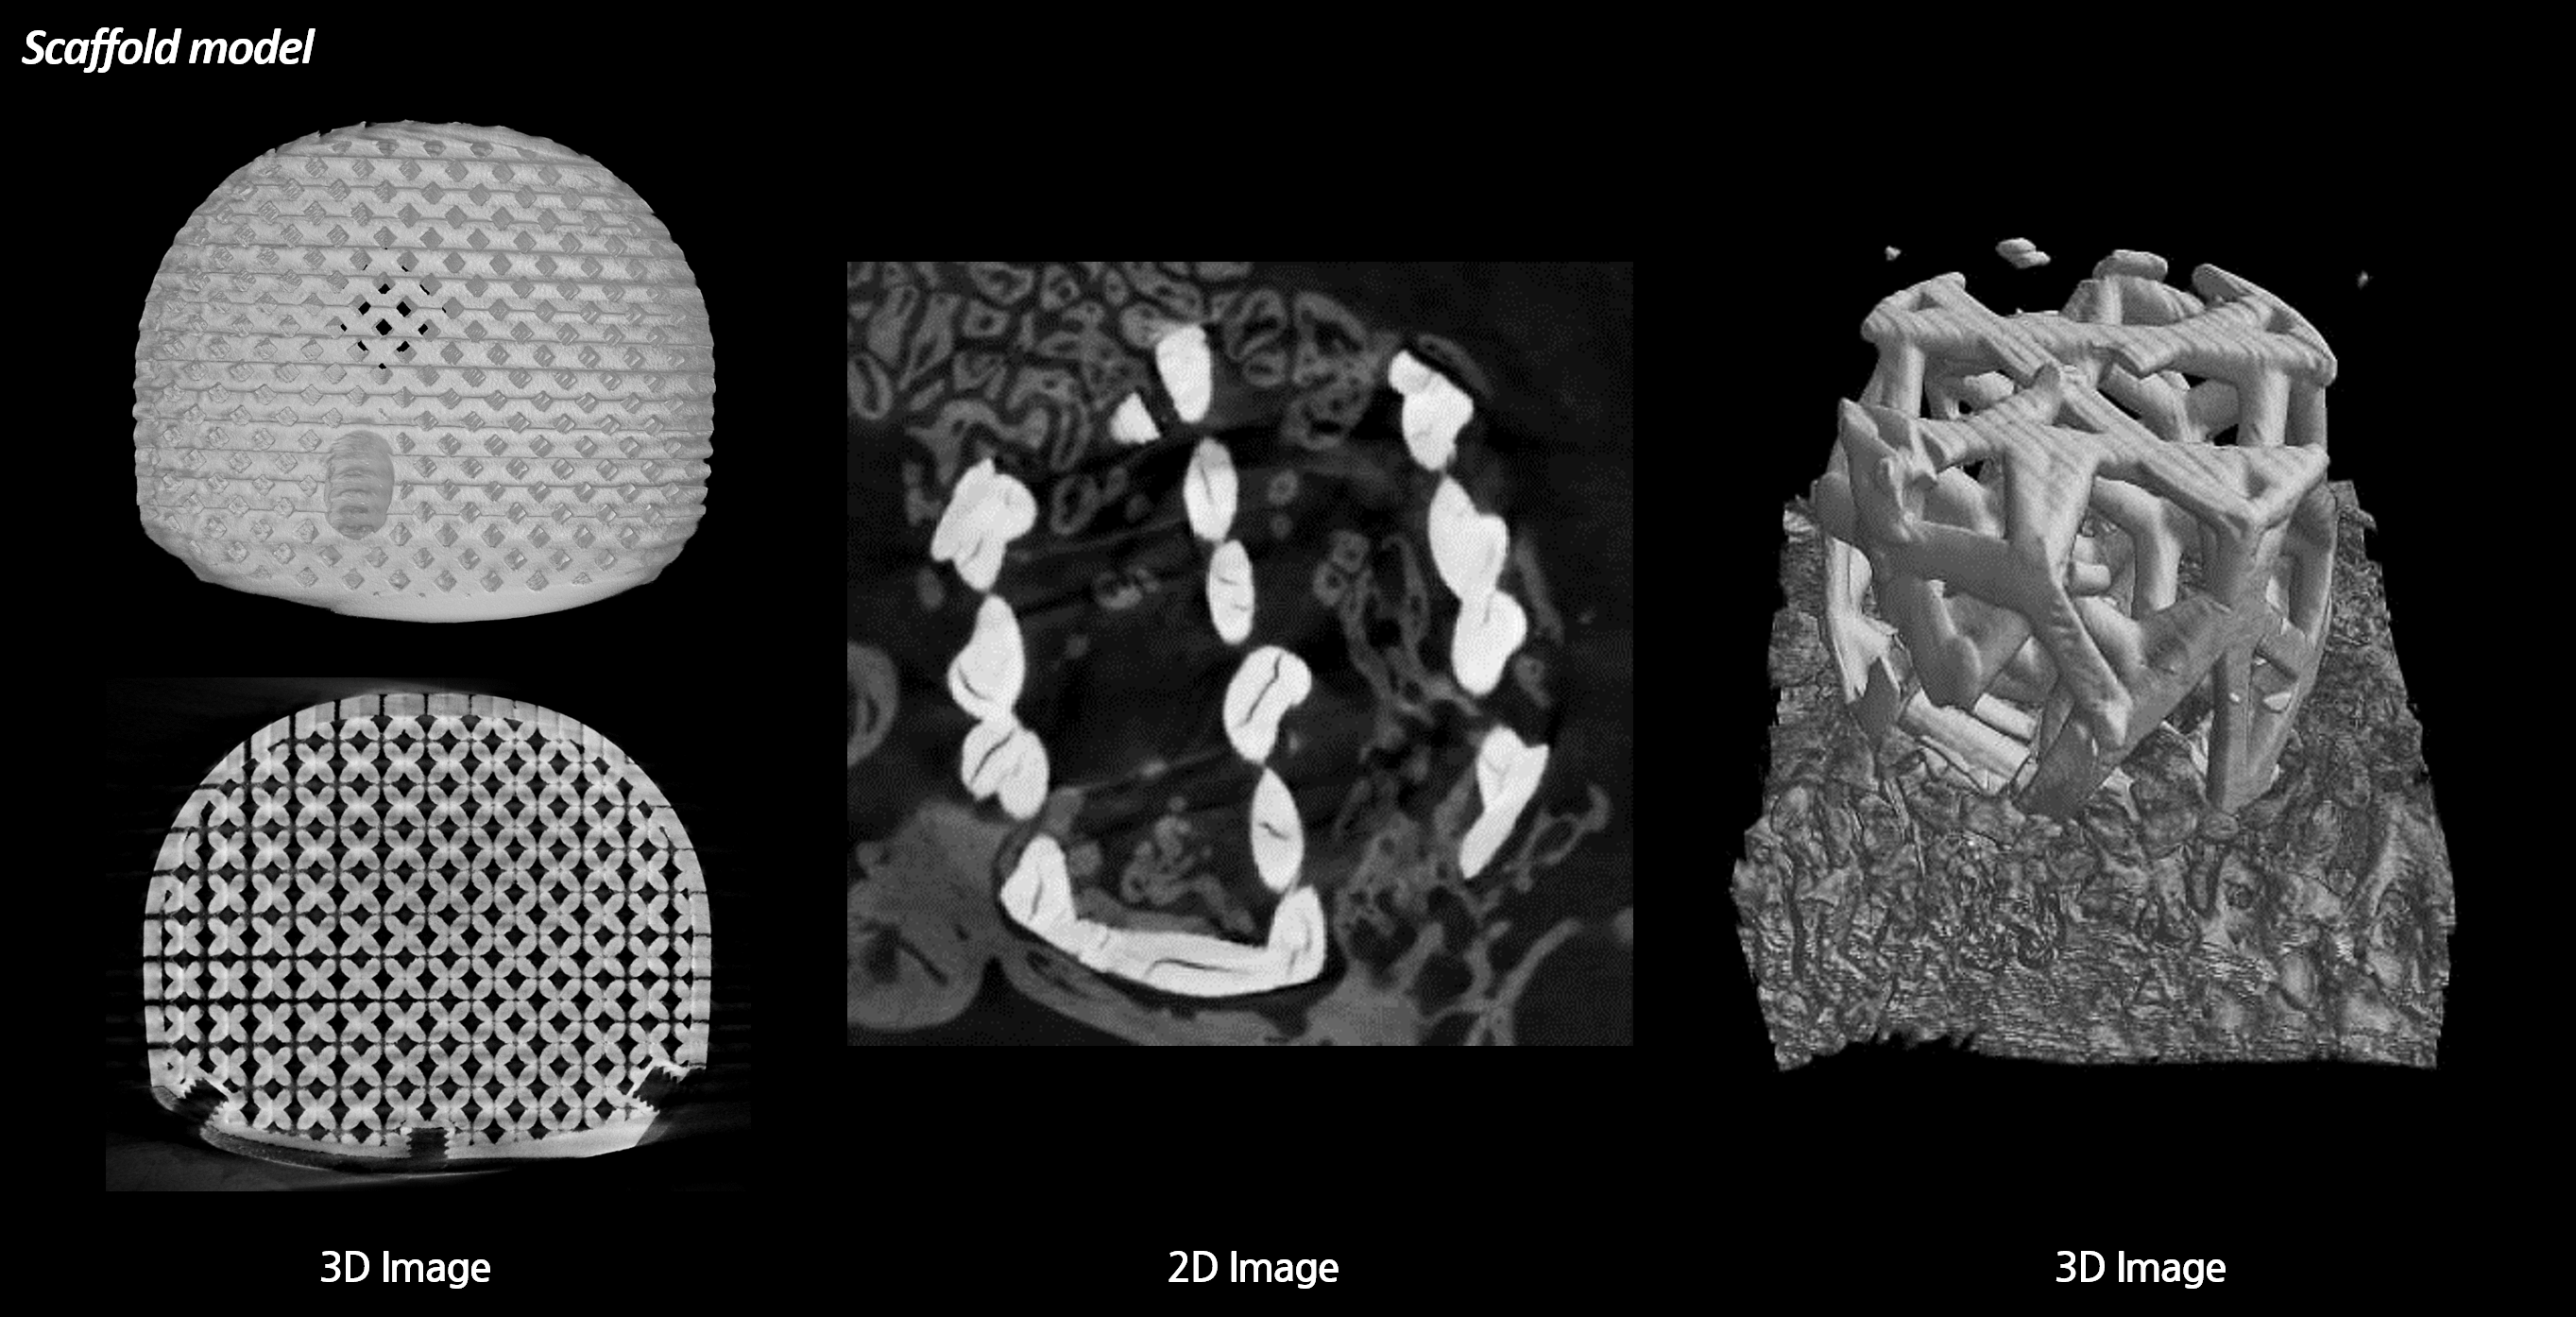

분석 예시

장비

이미지

2D & 3D 이미지 및 정량분석

3D printed lumbar cage